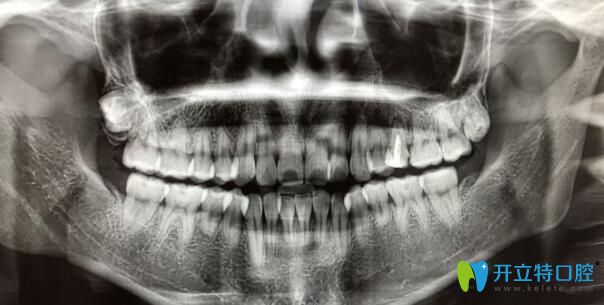

案例一:90后自述門牙牙根短做矯正感受:

首先我的門牙牙根很短,兩個(gè)醫(yī)生拒絕給我矯正的,但是我整牙欲望很強(qiáng)烈,冒著風(fēng)險(xiǎn)做了,也不知道以后會(huì)出現(xiàn)什么問題,門牙是否真的掉了,到時(shí)候再說吧,問題出了再去解決…

90后自述門牙牙根短做矯正感受

?牙齒矯正2個(gè)月:?感覺牙齒變化速度比較慢,目前牙齒還沒又松動(dòng)神馬的感覺。

牙根短做矯正效果